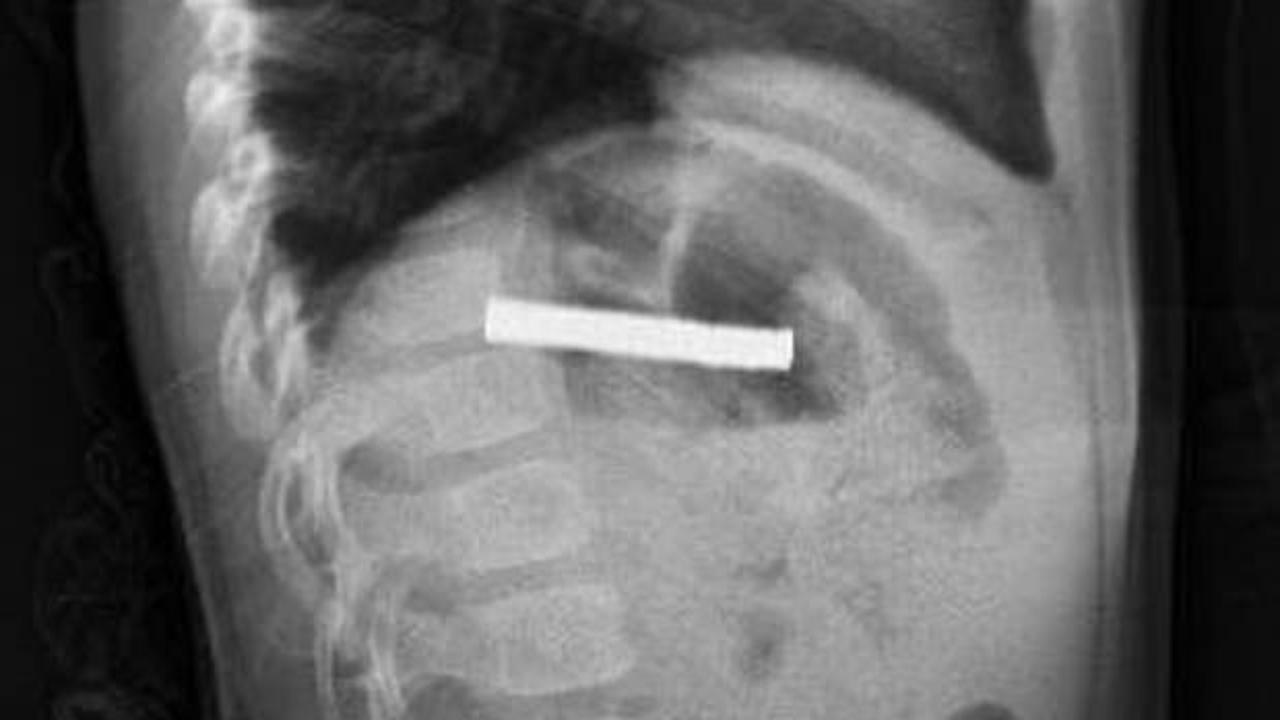

Elazığ'da 19 mıknatıs yuttuğu için yemek borusu ve mide girişi zarar gören 3 yaşındaki çocuk hastaya endoskopi yöntemi uygulandı. Yapılan uygulama ile 19 mıknatısların tamamı çıkarıldı.

Fırat Üniversitesi Çocuk Gastroenteroloji Hepatoloji ve Beslenme Bilim Dalı Başkanı Prof. Dr. Yaşar Doğan, çocuk hastanın yemek borusuna yapışmış 19 mıknatısı endoskopik yöntemle çıkardı.

Mıknatıslar uzun süre yemek borusunda takılı kaldığı için yemek borusu ve mide girişinde zedelenmeler olurken, çocuğun sağlık durumunun iyi olduğu ve taburcu edildiği öğrenildi.